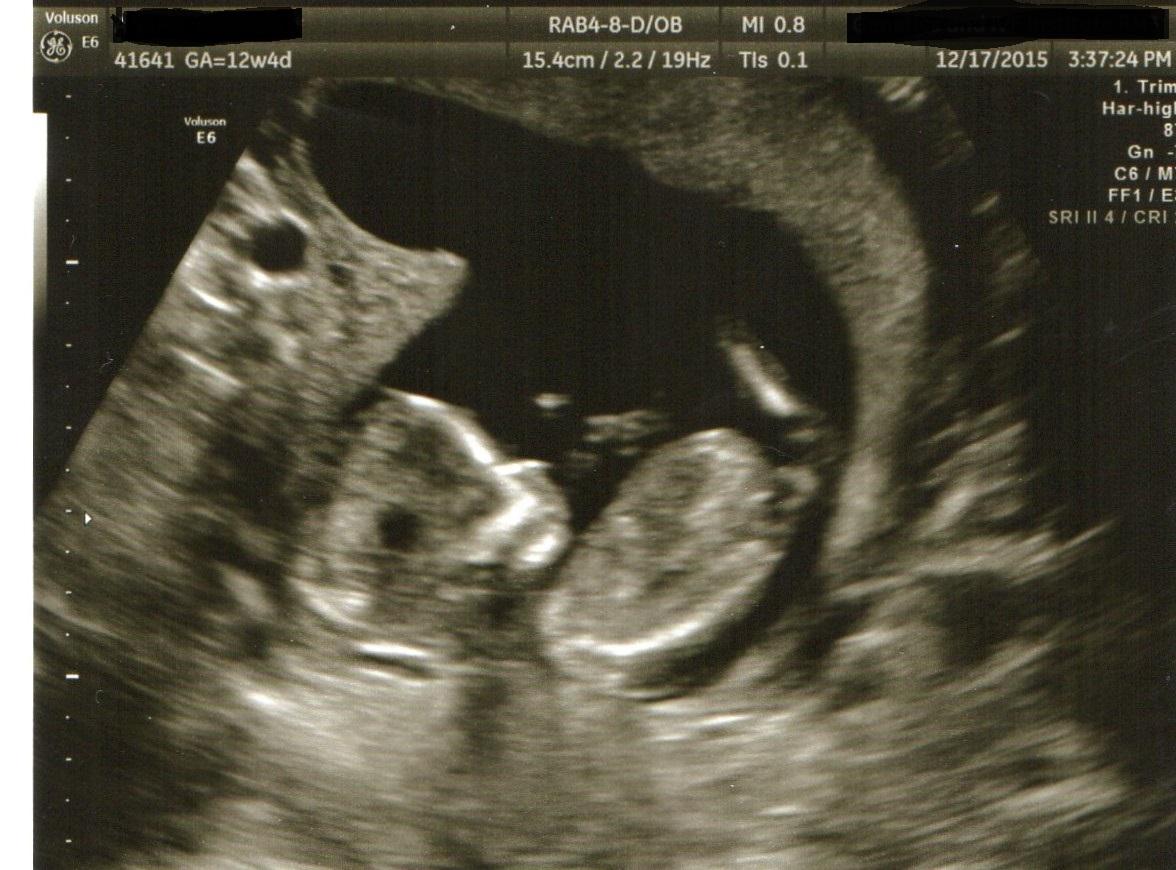

Our NT scan today revealed what the tech said was the most stubborn fetus he's tried to measure in some time. Got a picture with the tips of all 5 fingers up by their face. 12w4d, heart rate of 153 (I think).